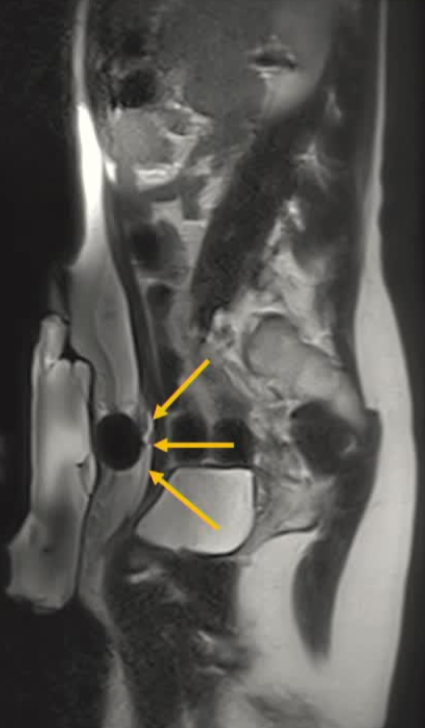

| 腹壁下病变 | MRI引导下 冷冻消融。装有热水的手套在皮肤表面保护皮肤 |

病灶位置:16个疼痛性目标病灶位于脐部(7/16,43.8%)、膈肌(4/16,25.0%)、腹股沟管(3/16,18.8%)和子宫肌肉层(即腺肌症,2/16,12.4%)。

影像引导方式:超声和横断面成像(CT或MRI)结合是最常用的影像引导方式(10/16,62.5%)。

保护措施:几乎所有干预都需要辅助保护措施,其中水分离术(13/16,81.3%)和水分离术与温盐水填充手套的皮肤保护结合(9/16,56.3%)是最常见的保护措施。